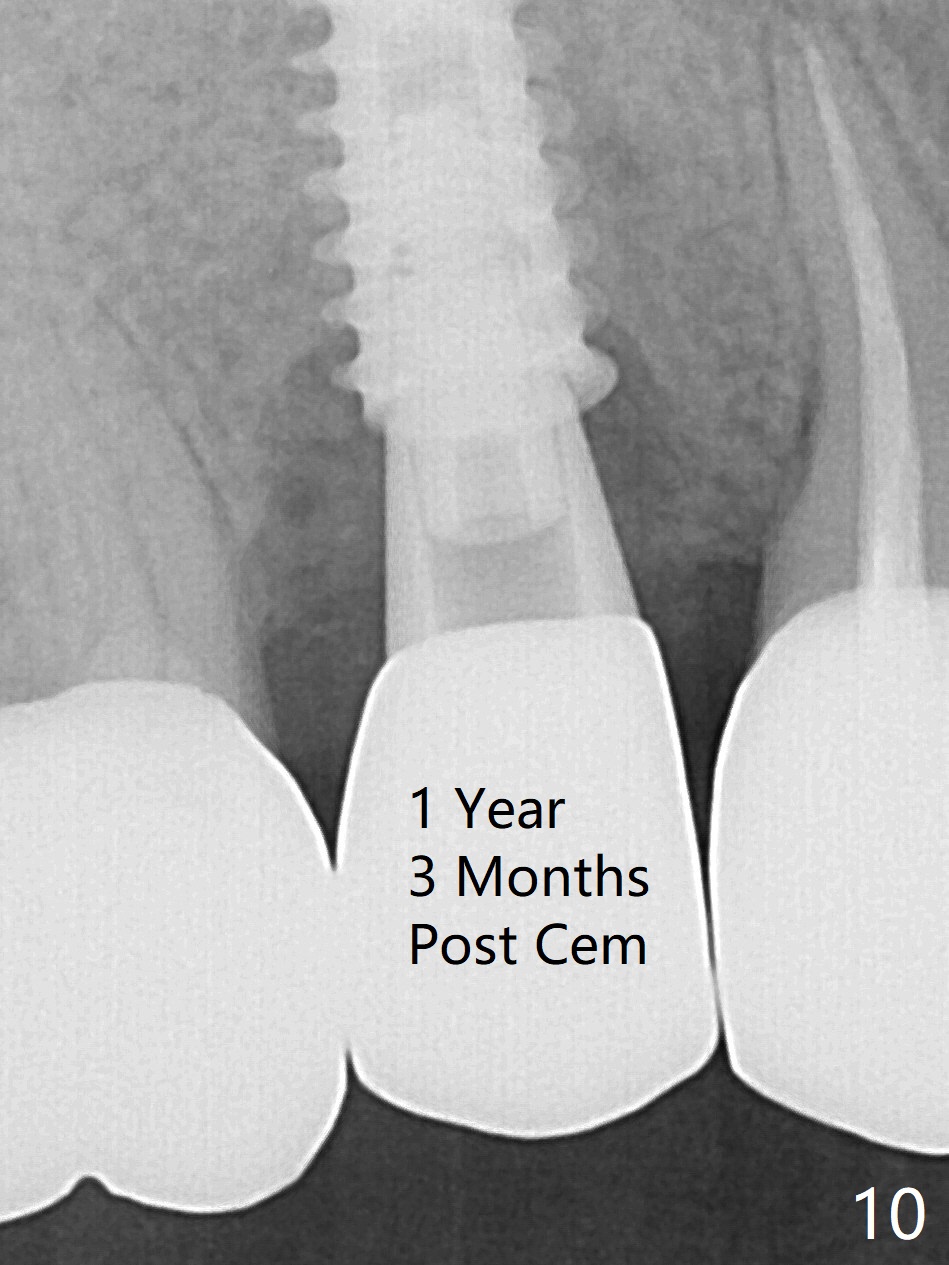

When the tooth #4 with vertical root fracture is extracted, the socket is large, approximately 6x10x10 mm (Fig.1 (mesiodistal x buccopalatal width x depth)). Osteotomy is established in the middle of the socket with 2 mm initial drill for 7 mm, 2.8 and 3.6 mm rounds drills (from DIO Sinus Master Kit) for < 7 mm, and 3.0 and 3.8 mm Magic Expanders. A 4x11 mm dummy implant is placed with insertion torque of 30 Ncm (Fig.2,3 (^: sinus floor)). There is a gap between the socket wall and the implant (*). To reduce the gap and periimplantitis, a 5x11 mm IBS implant is placed with insertion torque > 50 Ncm after further osteotomy using Magic Drills (Fig.4,5). Following placement of 5.5x4(4) mm abutment (A) and bone graft (data not shown), a splinted provisional is fabricated at #3 and 4. The provisional is stable 3 months postop (Fig.6,7). The peri-implant gaps (Fig.4,5) seem to disappear (Fig.6) with the help of bone graft. Bone graft appears to remain between the implant fins (Fig.7 arrows). Impression is taken 4.5 months postop (Fig.8,9). The abutment dislodges 4 months post cementation. After retightening, there is clearance for shim after use of 2 layers of thick articulating paper. Is the abutment screw too short? Or Titanium V is too hard for welding? The abutment/crown dislodges again 1 year 3 month post cementation; it appears that the fact that the implant is placed deep contributes to abutment screw loosening (Fig.10,11). An abutment screw will be buried inside the implant well 10 days post initial retightening.